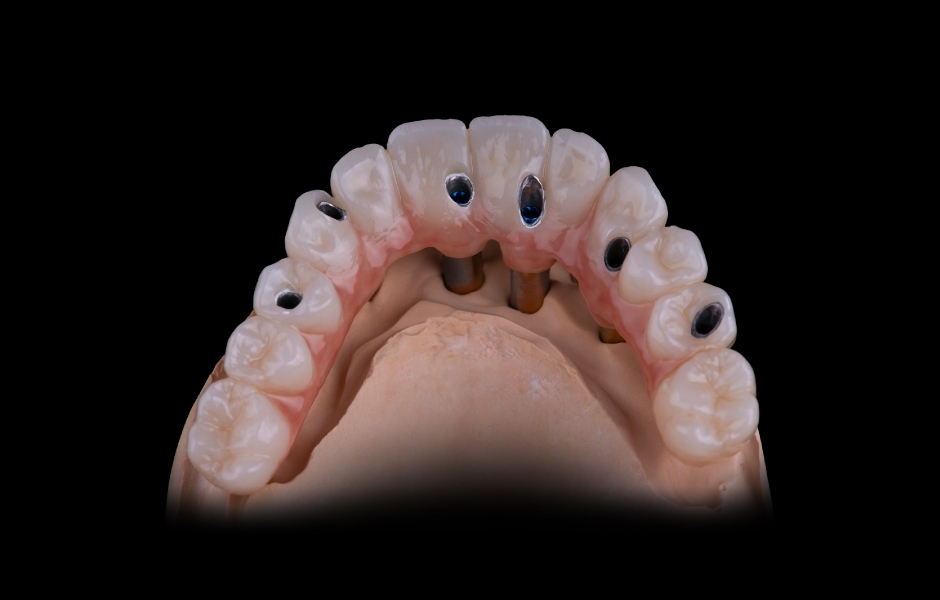

Obr. 5: Plánované implantáty z hlediska velikosti, délky a orientace.

Obr. 6: Návrh a výroba modulární chirurgické šablony s okluzálně-palatinálními vstupy pro šrouby.

Obr. 7: Návrh a výroba modulární chirurgické šablony s okluzálně-palatinálními vstupy pro šrouby.

Obr. 8: Návrh a výroba modulární chirurgické šablony s okluzálně-palatinálními vstupy pro šrouby.